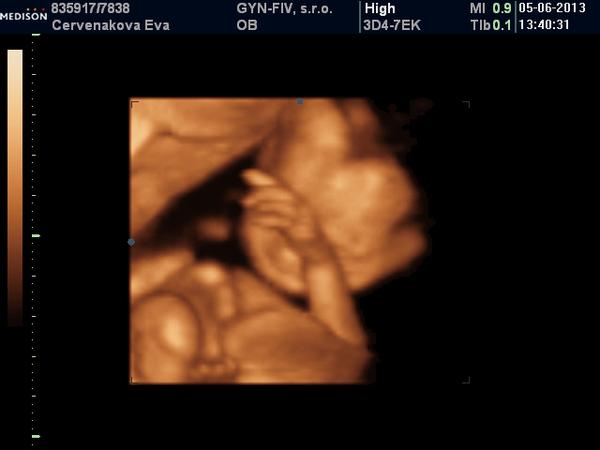

ahojte dievcata!! tak vcera som nestihla napisat ale 3D dopadlo dobre, babetko je zdrave.. A sme DIEVCATKO! takze manzel 4 dievcatko a ja 3 🙂bolo to kraaaaasne aj ked som mala pocit ze velmi dlhe a ze chuda malicka... bola v brusku inak riadne schulena... a ja vraj pohyby preto citim dole lebo je mala zadockom dole a tam kope a ze sa asi velmi netoci... no dufam ze miesta tam ma dost. akurat dr. hovorila ze na maternici mam stale miom 3,5 cm co je este spred tehotenstva a pritom iny sa tvarili ze tam nic nemam... a este ze mam taky tvar maternice ze sa mi dovnutra robi nejaka svalovina a ze to dr. zavadzalo aj pri robeni utz.. tak dufam ze to nie je nejaky problem ona tvrdila ze to nie je nejaky problem ale ja sa este spytat aj mojho dr. Malicka sa hybala kopkala ale nie nejak velmi. no lutovala som ju ked mi tak dlho robila to sono. fotky som pridala do svojho albumu a tu dam jednu.

@andy09 fu andy asi polhodinu a mne sa to uz zdalo vecnost, nie ze by som ju nechcela uz tak dlho pozerat ale chodila dr. s tou sondou po bruchu veeelmi dlho a bala som sa ze to malickej uz vadi... tak uz som jej asi 10 min. hovorila ze"nechajme ju uz ved to mi staci" a tak... a teraz zistujem ze som sa mohla este nejake veci popytat. no ale tam ta to nenapadne.. Tvoje uz bude v tom tyzdni baculatejsie, nasa mala ma okolo 300g a vy uz budete mat aj 500 a aj viac mozno takze to bude este krajsie. ale ja idem este aj v 26tt priblizne na 3d k dr. u nas . A vcera som kupila aj nejake vecicky pre malicku, pridam si do albumu nech mam radost. Kociky sme chceli pozriet ale uz sme nestihli...